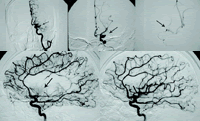

脑血管造影示,患者左侧大脑中动脉M1段完全闭塞(见图1,箭头所示),导丝引导微导管通过闭塞段动脉,远端有血流通过,在其远端注入尿激酶25万U,30分钟后经微导管于闭塞近端注入尿激酶25万U,30分钟后大脑中动脉完全开通(见图2),随后出现大脑前动脉闭塞,再次注入尿激酶25万U,1小时后大脑前动脉开通。, http://www.100md.com